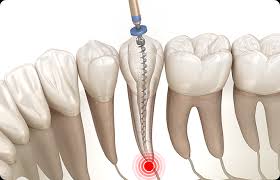

신경치료(근관치료)는 치아 내부의 손상된 신경(치수)을 제거하고, 그 공간을 소독한 후 밀봉하여 감염을 막는 치료입니다. 충치가 깊어져 신경까지 침범하거나 외상, 감염 등으로 인해 통증이 심할 때 시행됩니다.

치아를 뽑지 않고 살릴 수 있는 효과적인 치료로, 많은 사람들이 ‘신경을 죽인다’고 표현하지만, 실제로는 치아 내부의 감염된 조직을 제거하고 본래 치아를 보존하는 과정입니다.

- 감염 제거 및 소독: 근관 확대·세척